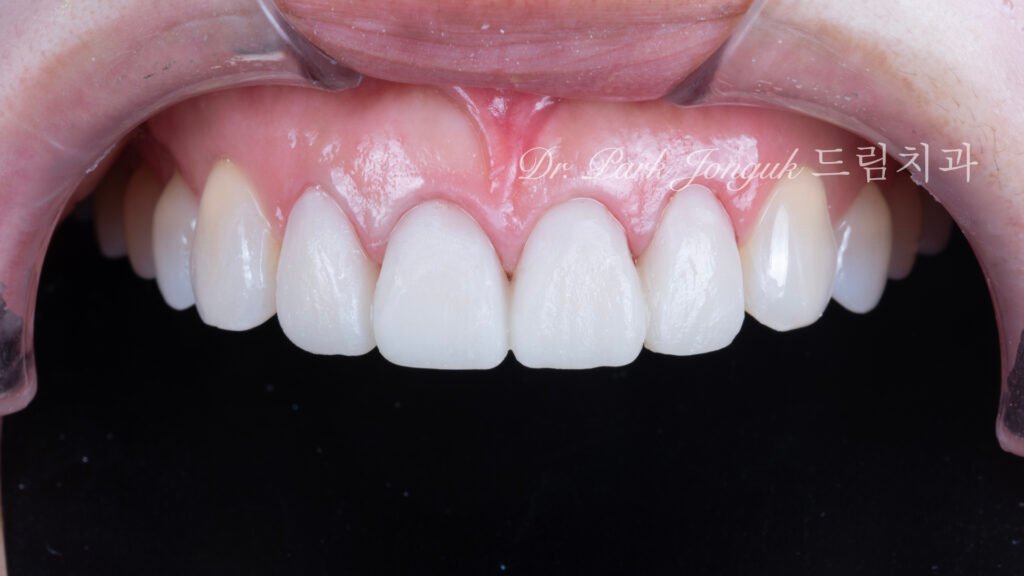

사진 8~11. 치료 후

투명감이 살아있는 자연스럽고 아름다운 라미네이트 올세라믹 크라운

핸드메이드 빌드업 방식으로 제작된 라미네이트는

투명감, 질감, 색감이 완벽하게 조화를 이루며 자연치아와 구분이 어려웠습니다.

환자분은 거울을 보고 “이게 진짜 아름다운 치아네요”라며 감탄하셨습니다.